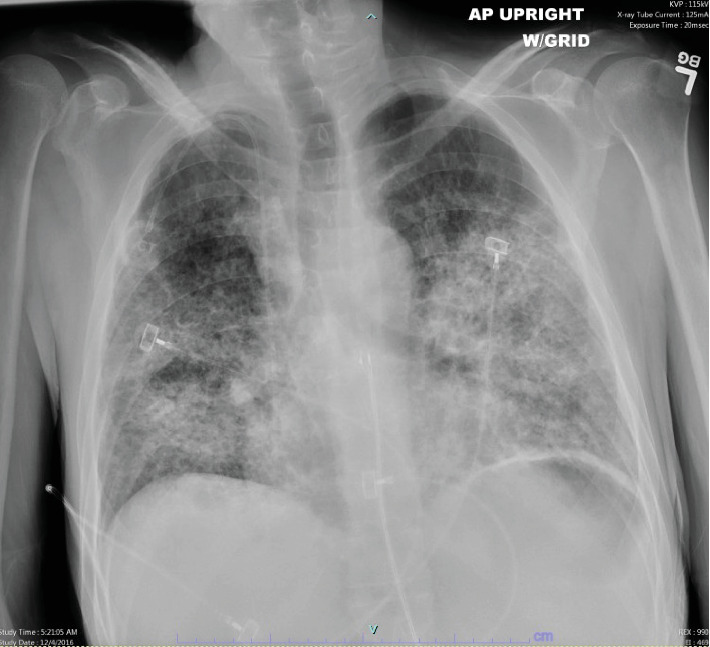

丝裂霉素C (MMC)肺炎导致急性呼吸窘迫综合征(ARDS)是一种罕见的危及生命的MMC不良反应。诊断MMC肺炎可能具有挑战性,因为更常见的病因(如细菌感染)往往是首先针对的目标,因为患者因化疗而免疫功能低下。我们报告了一例中年男性服用MMC而不同时服用长春花生物碱的病例,他发生了继发于MMC肺炎的ARDS,需要插管和重症监护。患者在服用抗生素多日后,经类固醇治疗恢复,未发现感染性病因。这个病例强调了认识到MMC是可能导致急性呼吸窘迫综合征和死亡的肺炎的潜在病因的重要性。

Mitomycin C (MMC) pneumonitis leading to acute respiratory distress syndrome (ARDS) is a rare and life-threatening adverse reaction to MMC. Diagnosing MMC pneumonitis can be challenging as more frequent etiologies such as bacterial infections are often targeted first due to patients being immunocompromised from chemotherapy. We report a case of a middle-aged male who was administered MMC without concomitant vinca alkaloid, who developed ARDS secondary to MMC pneumonitis requiring intubation and intensive care. The patient recovered with steroid treatment after being on antibiotics for many days, and no infectious etiology was ever identified. This case emphasizes the importance of recognizing MMC as a potential cause for pneumonitis which can lead to ARDS and death.